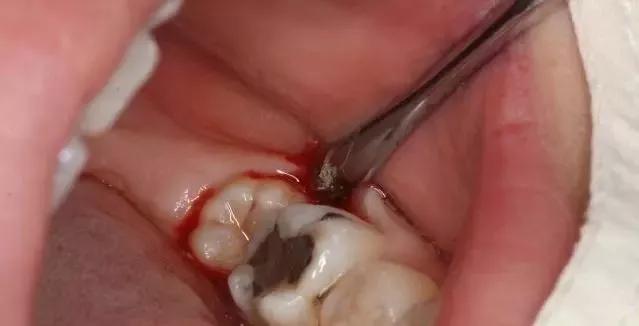

拔牙结束并不表示口腔里的问题也随之完结。拔牙后最容易发生出血和感染,因此有许多细节需要了解和掌握:

拔牙后24小时内有轻微疼痛,吐出的唾液里混有些粉红色血水或血丝都是正常的,可在医师的指导下服用适量的消炎镇痛药。但值得注意的是,疼痛和出血应该是越来越轻,越来越少。如果几天后还有持续出血或疼痛,甚至出现明显的头晕心慌等不适症状,就应立即到医院复诊,查明原因后及时处理。